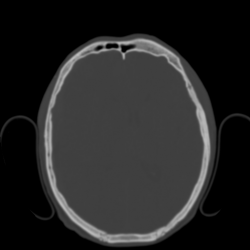

В костном режиме видно линейный перелом лобной кости слева:

Как видно по МСКТ-сканам формирование субдуральной гематомы было типу "противоудара". Молодой человек был прооперирован, нейрохирурги сказали что у него было около 200мм крови.